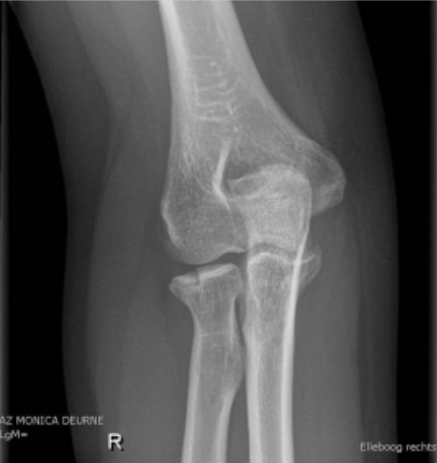

Fractura presente en esta radiografia

Intertrocanterica

Mecanismo de lesion de esta fractura

Jovenes: Alta energia

Ancianos: Caisa simple, impacto directo en trocanter mayor

De acuerdo a la clasificacion de EVANS esta fractura se considera

Inestable

Estable

Tratamiento de fractura intertrocanterica

Idealmente <48hrs post lesion

Clavo endomedular con tornillo deslizante

Tratamiento de fractura intertrocanterica en pacientes con comorbilidades graves

Protesis parcial (De Thompson)